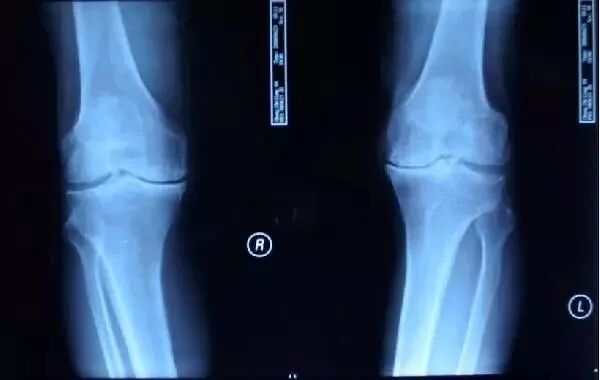

膝关节骨性关节病以中老年阶段为发病高峰期,尤其是肥胖的女性,发病率更高。该病的主要表现为:膝关节持续的运动性疼痛,即下蹲痛,上下楼梯痛,尤以下楼梯更甚,并有功能障碍,常受天气影响。其特点是:病程长,病情时好时坏,迁延难愈。该类患者摄片时多有膝关节的退行性改变,包括髌骨软化,髌骨上下缘骨质增生,软骨破坏,骨刺形成,关节间隙狭窄,关节面不平等改变。据此,传统观点认为:膝关节骨性关节病是由于局部骨质增生,引起关节间隙狭窄,从而形成运动性疼痛和功能障碍,即骨性观点。依据这一理论,该类患者若要得到彻底治愈,势必应行开放性手术切除骨赘,才能解除疼痛,然而在临床实践中,相当一部分患者并未达到理想效果。而且,通过长期临床观察发现,大部分患者膝关节的X线退化性征象和膝部疼痛并没有平行关系。